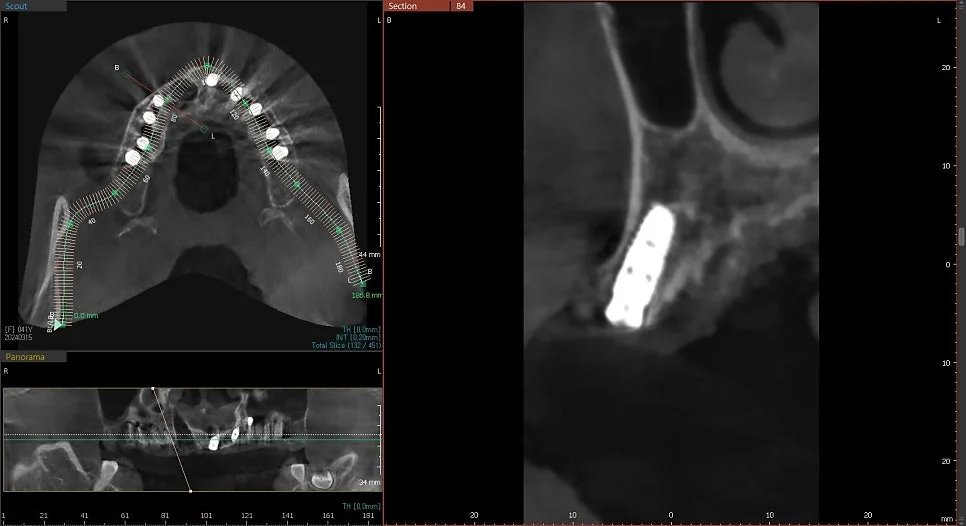

CBCT 단면 – 각 임플란트 개별 검증

CT 상에서 하얀색인 임플란트가 1. 온전히 뼈 안에 잠기게(1~2mm 깊게) 그리고 2. 가급적이면 입천장 쪽으로 식립되었다면 잘 심긴 임플란트입니다. (입술 쪽 뼈는 쉽게 흡수됩니다ㅜ)